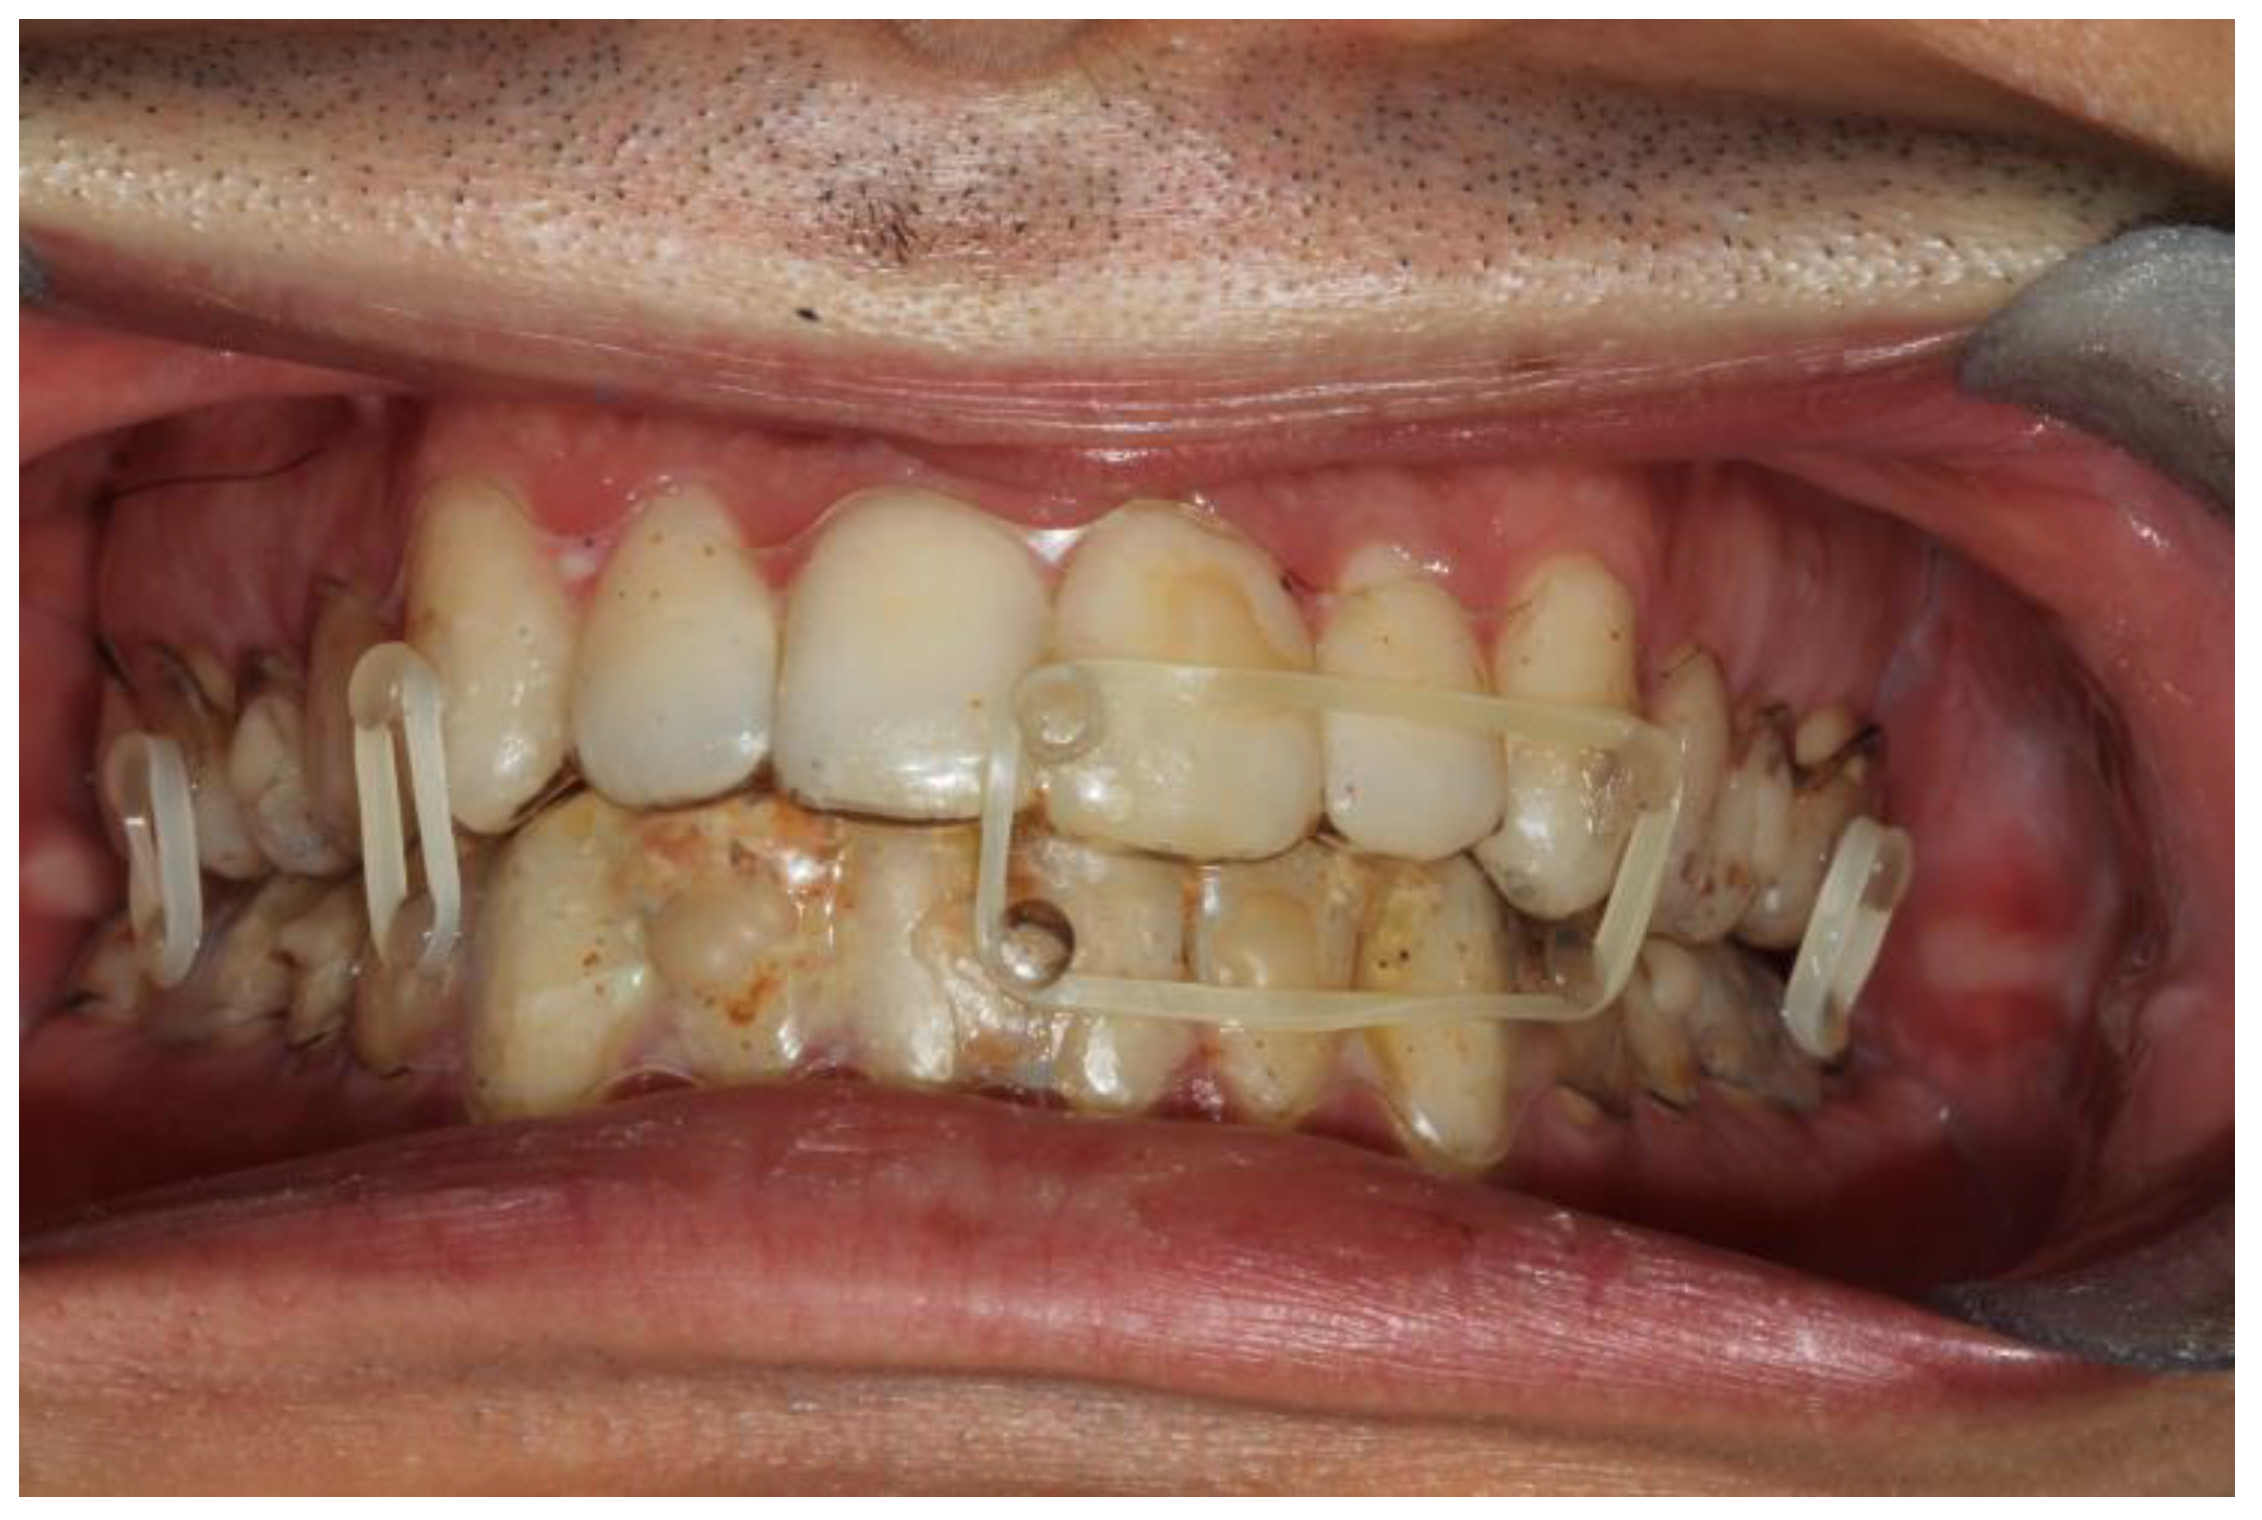

Figure 1. Intraoral view of patient 2. It is possible to see the coronal fracture of element 4.2; the fitting of the splints is adequate and so is the fixation.

The second patient was a male, aged 20, with a right condylar diacapitular fracture (Figure 4). The patient also presented a coronal fracture of the element 43 due to the trauma. The other teeth were sound, but the 37 was unerupted. He presented a slight class III malocclusion and a posterior open bite on the left. In this case, there was the need to not exert force on the fractured tooth, and to balance the traction points of the rubber bands despite the absence of the 37, avoiding extrusive forces on the 27.

The fixation strength of the intermaxillary fixation was considered adequate in both cases (Figure 5 and Figure 6).